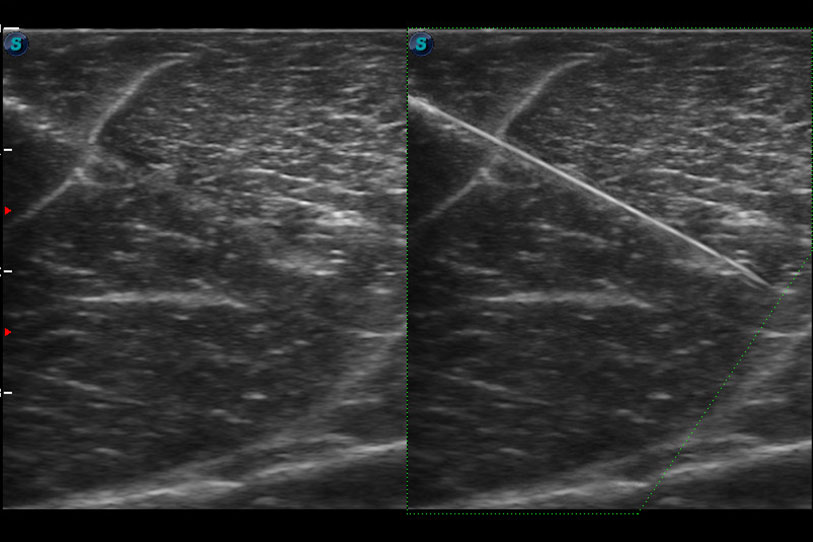

增強穿刺針在動物解剖結(jié)構(gòu)中的位置,提高穿刺介入的安全性和準確性。